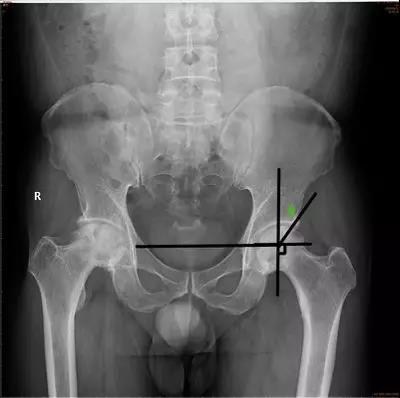

- CE角(Wiberg 的中心边缘角):即两侧股骨头中心连线的垂线和髋臼外缘股骨头中心连线所成的夹角。

- 正常值:20°~35°

- 临床意义:主要用于评估髋臼的包容性,髋臼发育不良时夹角变小。

- Sharp角:即双侧泪滴下端连线与泪滴下端至髋臼上缘连线所成的角。

- 正常值:33°~38°

- 临床意义:<32°很少见且无临床意义39°~42°为正常值的上限,42°~47°需动态观察,>47°可认为异常。评价髋臼发育和髋臼对股骨头的覆盖情况。